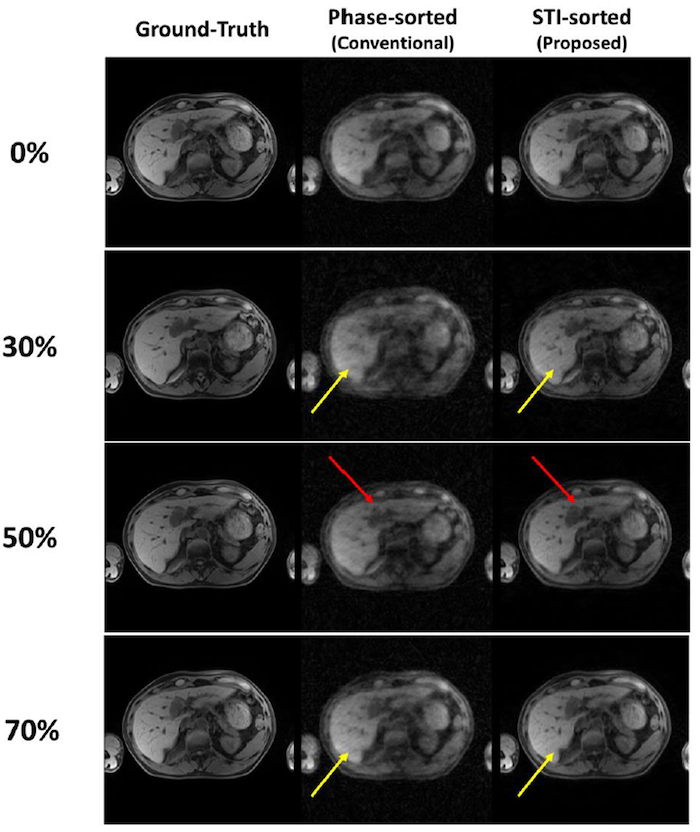

Computed tomography (CT) is the primary imaging modality in modern radiotherapy, offering unique tissue electron density information for accurate dose calculation. Over the last decade, the application of magnetic resonance imaging (MRI) in radiotherapy has emerged as a significant research topic. MRI offers superior soft tissue contrast for disease identification, zero risk of ionizing radiation and the potential to provide physiological information in addition to anatomical details. This body of work advances MRI applications in various aspects of radiotherapy, including four-dimensional (4D) MRI for tumor motion assessment, rapid MR image reconstruction and MRI-specific image biomarkers for radiotherapy. Some of these findings have been incorporated into medical physics practice guidelines within our community.

MRI application in image-guided radiotherapy

• Wang C*, Subashi E, Yin F-F, Chang Z, Cai J. A Spatiotemporal-Constrained Sorting Method for Motion-robust 4D-MRI: A Feasibility Study. International Journal of Radiation Oncology* Biology* Physics 103(3): 758-766 (2019)